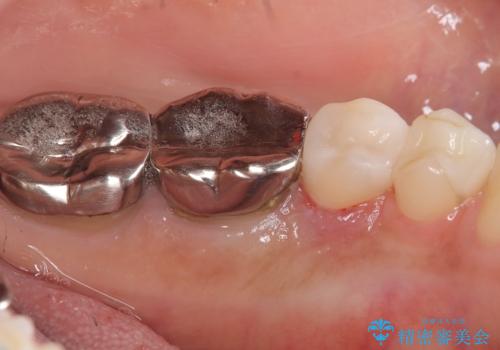

メタルインレーを除去したところ、二次カリエスうを確認したため除去・CR裏層の後、形成・印象しています。

セラミックインレーの接着操作時にはラバーダム防湿を行っています。